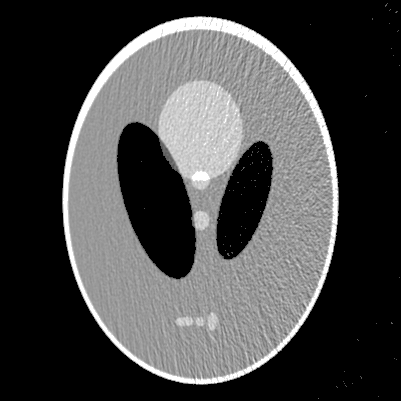

In this section, we will validate the performance of the proposed method by numerical experiments.

For this purpose, a SPECT version of the Shepp-Logan phantom(see figure 1(a), [1]) was used under various conditions.

The attenuation map we used is equal to a constant inside the ellipse shown in figure 1(b). Although we used different values in the ellipse for different experiments to test the stability of the proposed methods, we only illustrate the reconstructed images in figures 2 and 3 for and , which are sufficiently large

for the medical applications of SPECT(see [1] for details).

In the experiments, perfect projection data at 1000 views sampled over evenly with 400 rays

are created via the eRt formula (2).

In order to test the stability and robust of the proposed method about noise, the data were Poisson

noised by the procedure used in [1].

The reconstructions were discretized in a grid.

The proposed method was performed for various computer-simulated data, including perfect, noisy, non-truncated and truncated data. Figure 2 displays the reconstructed images from perfect data, while figure 3 displays the reconstruction from noised data for and . The images in top row are reconstructed from non-truncated projection data, while these in the bottom row are reconstructed from the truncated data such that any measurement corresponding to a line not passing through the rectangular box in figure 1(a) was discarded.

From figures 2 and 3, we can see that the presented algorithms can carry out the reconstruction of SPECT efficiently. As our expectation, the distortions in the reconstructions raise with the increase of the attenuation coefficient . The profiles of the reconstructions in figure 2 at are displayed in figure 4. Similar to [1], we have the same observation that the noise in the reconstructions appears strongly spatial variant, for which the reason is the weight variant in (3)(see [1] for details).